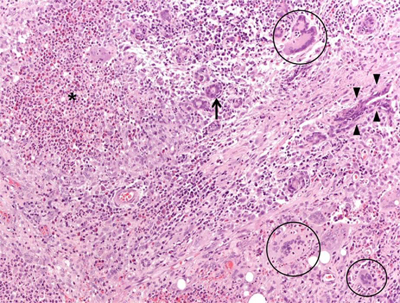

A 45-year-old female came to our attention with a six-month history of ulcerative mass in her right breast. Definitive pathology on breast lesion (Figure 1) documented the presence of a granulomatous mastitis with necrotic foci (asterisk), giant multinucleated cells (circles), and normal breast ducts in transversal (arrow) and longitudinal section (arrowheads) trapped by neutrophilic-eosinophilic infiltrate. Pathologist found no signs of malignant lesions. During the following months, the patient developed worsening cough, shortness of breath, nasal obstruction with hematic discharge, and hearing loss. Chest computed tomography (Figure 2) showed marked wall thickening of the right main bronchus (asterisk), stenosis of the left main bronchus (black arrowheads), and segmental atelectasis in the upper lobe of the left lung (white arrowheads). Paranasal sinuses computed tomography (Figure 3) showed a perforation of the nasal septum (asterisks), absence of the anterior half of the left inferior turbinate (white arrows), and atrophy of the upper lateral cartilages (white arrowheads). Fiberoptic rhinopharyngoscopyscopy documented the presence of extensive crusting rhinitis. Blood tests revealed high levels of antineutrophilic cytoplasmic antibodies with cytoplasmic pattern (c-ANCA). These findings were consistent with diagnosis of granulomatosis with polyangiitis. The patient was put under oral prednisone 1 mg/kg daily and cyclophosphamide monthly pulse therapy, with progressive improvement of breast and nasal lesions. She has currently reached a clinically stable NYHA Class II and is treated with prednisone 15 mg daily, methotrexate 15 mg weekly, and n-acetilcysteine 600 mg daily. She needs periodic endoscopic dilatations of bronchial stenosis.

Figure 1

Microphotograph (magnification: 40X) showing a granulomatous mastitis. Mammary parenchyma is characterized by the presence of dense necrotic foci (asterisk), giant multinucleated cells (circles), and normal breast ducts in transversal (arrow) and longitudinal section (arrowheads), trapped by neutrophilic-eosinophilic infiltrate.